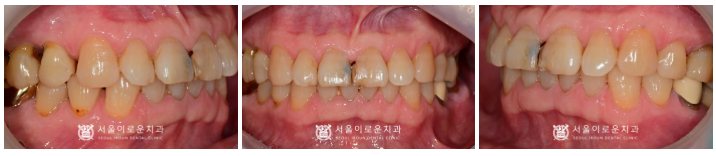

임플란트와 크라운 보철 치료가

마무리 된 사진입니다.

환.자분께서는

통증이 사라지고,

앞니가 자연럽고 예쁘게 되었다며

치료 후 정말 만.족해하셨답니다!

✅ 전 > 후 ✅

(2024.06.07ㅡ>2024.11.23)